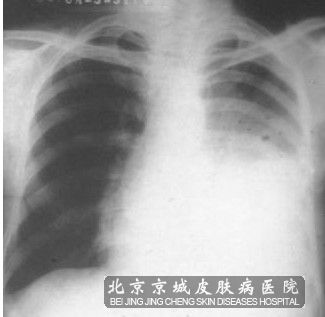

肉眼观察可见,肿物一般呈灰白色,如果发生坏死颜色 则呈灰黄色;肿物与周围的肺组织分界不是很清楚,较大的肿瘤,癌组织常坏死脱落,形成癌性空洞。瘤组织破坏支气管壁,浸润周围肺实质,或向腔内突起,受累的支气管腔会明显变狭窄。

肺鳞癌组织学特点与其他部位鳞癌基本一致。其基本结构特点是:癌巢具有分层结构,即癌周*呈基底*样的排列,而巢中央癌*分化比较成熟,胞浆丰富嗜酸似棘*。

其中的癌巢*会出现不同程度的*角化、角化珠形成或伴有*间桥。根据癌*角化程度不同,经典型肺鳞癌分为高分化鳞癌、中分化鳞癌和低分化鳞癌。而低分化鳞癌多见,高分化鳞癌少见,中分化鳞癌居于两者之间。中分化鳞癌和低分化鳞癌约占肺鳞癌的90 。